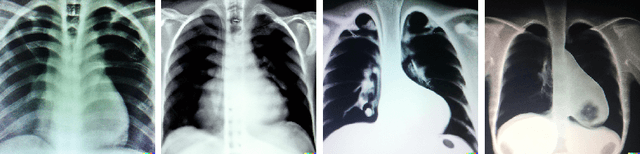

Abstract:Generative models are becoming popular for the synthesis of medical images. Recently, neural diffusion models have demonstrated the potential to generate photo-realistic images of objects. However, their potential to generate medical images is not explored yet. In this work, we explore the possibilities of synthesis of medical images using neural diffusion models. First, we use a pre-trained DALLE2 model to generate lungs X-Ray and CT images from an input text prompt. Second, we train a stable diffusion model with 3165 X-Ray images and generate synthetic images. We evaluate the synthetic image data through a qualitative analysis where two independent radiologists label randomly chosen samples from the generated data as real, fake, or unsure. Results demonstrate that images generated with the diffusion model can translate characteristics that are otherwise very specific to certain medical conditions in chest X-Ray or CT images. Careful tuning of the model can be very promising. To the best of our knowledge, this is the first attempt to generate lungs X-Ray and CT images using neural diffusion models. This work aims to introduce a new dimension in artificial intelligence for medical imaging. Given that this is a new topic, the paper will serve as an introduction and motivation for the research community to explore the potential of diffusion models for medical image synthesis. We have released the synthetic images on https://www.kaggle.com/datasets/hazrat/awesomelungs.